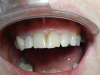

Figure 10 shows the final result. This case involved compromise; because of the patient's occlusion, the case had to be ramped out slightly; however, it is still more ideal than No. 10. The visual contour could have been tweaked more with a CO2 laser, but the patient declined. She was tired of the flipper and thus didn't want any more site work around the healing cap. She was ready for the process to be over. The implant was somewhat lighter than the surrounding teeth, but that was intentional because the patient planned to bleach her front teeth. Although some of her decisions were not what every dentist may necessarily agree with, the patient's happiness was the ultimate goal, and the result was fairly pleasing.

Fig 10. Final result.

Figure 10